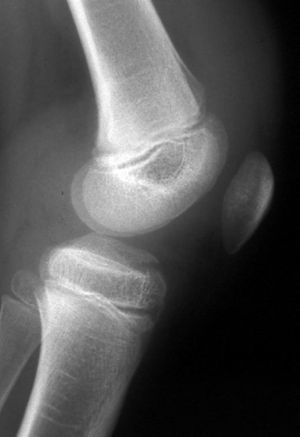

Estas lesiones se clasificaron por Meyers & McKeever en tres tipos (fig. 1): el tipo 1 que se caracteriza por un mínimo desplazamiento, el tipo 2 se caracterizaría por un desplazamiento de un tercio o una mitad en el plano sagital. Se denominan lesiones tipo 3 aquellas con desprendimiento total y desplazamiento del fragmento. Zaricznyj15 ha dividido más el tipo 3 en 3A sin luxación y 3B con luxación a dorsal. Radiológicamente la clasificación se realiza con la proyección lateral (fig. 2).

Figura 2. Proyección lateral de una rodilla con una lesión tipo 2.